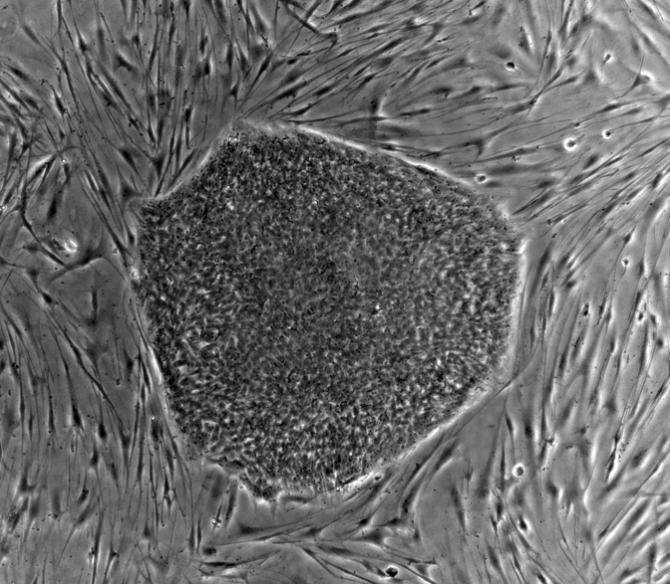

人類胚胎干細(xì)胞(hES)

干細(xì)胞一般有兩種來(lái)源,一種少部分存在于成年個(gè)體的組織器官中,例如:我們?nèi)绻ド倭揩I(xiàn)血,并不會(huì)馬上死掉,骨髓中的造血干細(xì)胞會(huì)馬上動(dòng)員起來(lái),分化為血液細(xì)胞,這樣你又可以活蹦亂跳了。而另外一種,功能更為強(qiáng)大,從發(fā)育早期胚胎分離得到的胚胎干細(xì)胞,它與成體干細(xì)胞不同,具有更高的多能性,可以轉(zhuǎn)變?yōu)槿梭w的任何的細(xì)胞、組織甚至器官,是一種真正萬(wàn)能細(xì)胞。